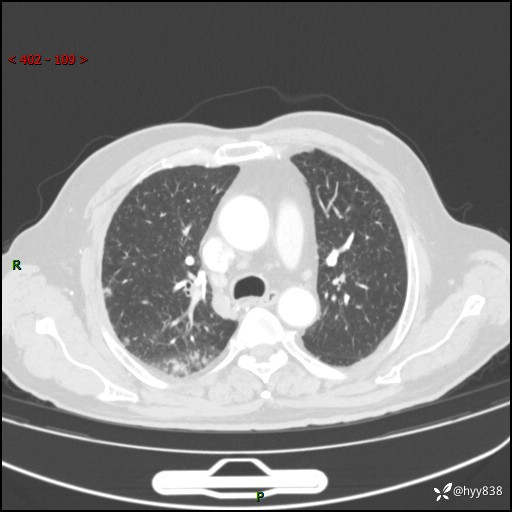

现病史:患者4月前无明显诱因后背正中间疼痛,间断阵痛,无低热、咳嗽,盗汗、咯血、胸痛、喘气等不适,2024-2-25当地市第二人民医院胸部CT提示“1.双肺感染病变;2.右肺中叶结节灶;3.双肺肺气肿并肺大泡4.主动脉及冠脉硬化,今为求明显结节性质遂来我院门诊就诊,门诊以“肺占位”收治入院。 起病以来,患者精神饮食睡眠一般,大小便正常,体力体重无明细变化。

胸部CT平扫(2024.2)